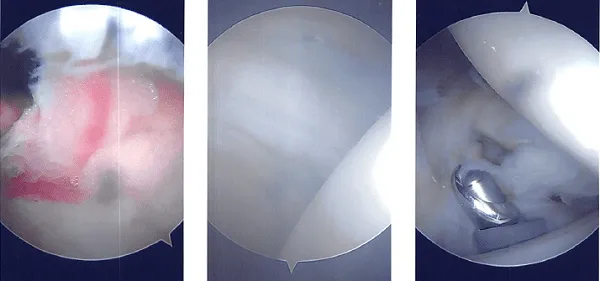

Se decidió hacer acromioplastia. Tras limpiar con una varita térmica y una fresa, se realizó una acromioplastia. La articulación AC fue revisada tras una acromioplastia completa y se encontró degeneración. Se planeó la excisión de la clavícula distal. La clavícula distal se extrajo con una varita y luego una fresa.

Se le retiró el último centímetro de la clavícula distal. Se capturaron y almacenaron las imágenes finales. Se usó nylon #4-0 para el cierre. Tras ser extubado, el paciente fue trasladado a la zona de recuperación.